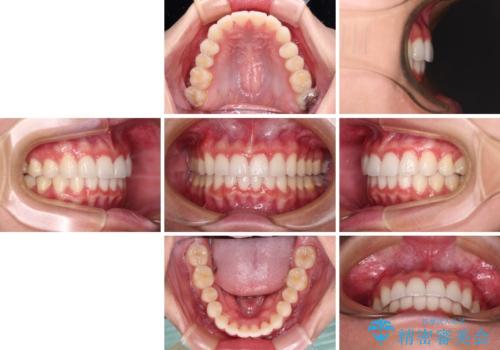

飛び出した前歯と黄ばんだ歯 ホワイトニングしながらマウスピース矯正

歯と歯の間を削ることで、飛び出した前歯が引っ込み、スッキリとした口元となりました。

歯の黄ばみも改善され、明るい歯並びとなりました。